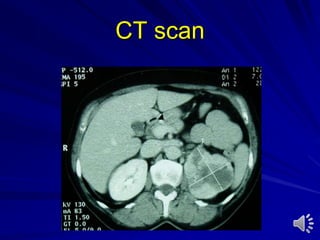

Computed tomography (CT) scan

With or without contrast medium

Indications:

– Stones

– Trauma

– Tumours

– Scaring of retroperitoneum

– Lymphadenopathy in genitourinary tumors

– Metastatic dissease

CT Scan